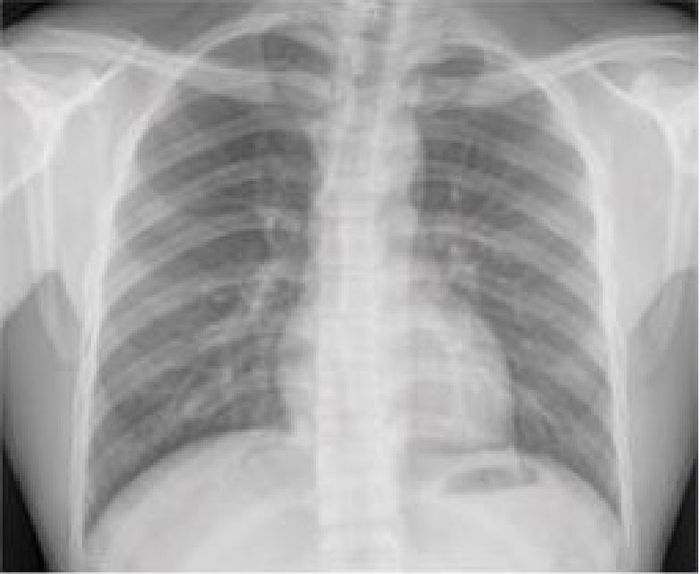

CHICAGO – Researchers have developed a deep learning model that uses a single chest X-ray to predict the 10-year risk of death from a heart attack or stroke, stemming from atherosclerotic cardiovascular disease. Results of the study were presented today at the annual meeting of the Radiological Society of North America ( RSNA ).

Dr. Weiss and a team of researchers trained a deep learning model using a single chest X-ray (CXR) input. They developed the model, known as CXR-CVD risk, to predict the risk of death from cardiovascular disease using 147,497 chest X-rays from 40,643 participants in the Prostate, Lung, Colorectal, and Ovarian Cancer Screening Trial, a multi-center, randomized controlled trial designed and sponsored by the National Cancer Institute.

“The beauty of this approach is you only need an X-ray, which is acquired millions of times a day across the world,” Dr. Weiss said. “Based on a single existing chest X-ray image, our deep learning model predicts future major adverse cardiovascular events with similar performance and incremental value to the established clinical standard.”